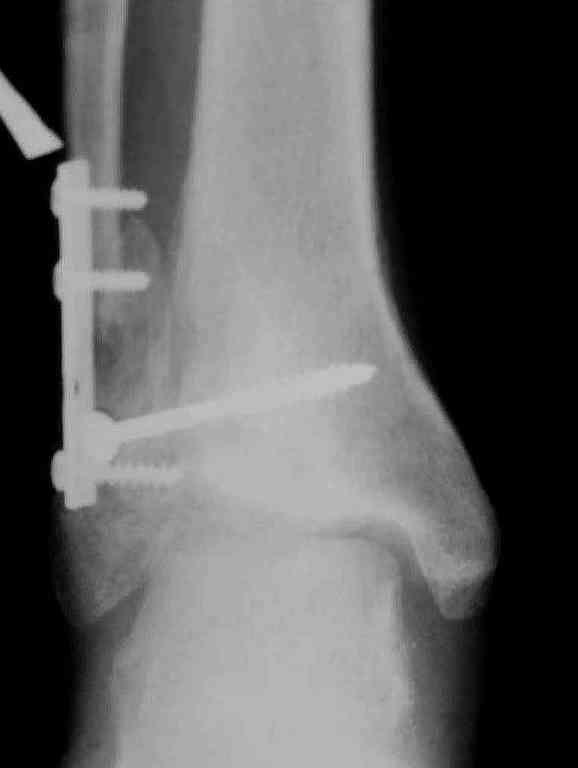

Вторая пациентка 34 лет, перелом получала в Испании, где от операции отказалась, дома по приезду сняла скотчкаст и лечилась у костоправов, нагрузка с 3 недели. Операция через 3 мес после травмы. Остеотомия м-б кости, фиксация пластиной, восстановление МБС. Так как медиальная лодыжка подтянулась, суставная щель на ЭОП контроле нормализовалась ограничились латеральным доступом. Реконструкцию заднего края не пытались сделать тк там уже прослеживалась консолидация, а сминать эпиметафиз не хотелось. В настоящее время ходит с тростью \три месяца после операции\, сустав нестабилен-слабость дельтовидной связки. Супинатор и плотные кроссовки дают возможность длительно ходить. Первый снимок сделан в Испании после репозиции, второй через 2 месяца после травмы перед операцией, третий-через 3 мес после операции.

Спасибо за вложенную схему , ранее она нам не попадалась.Согласен с Алексеем, что в обоих случаях не удалось восстановить длину фибулы.По вопросу о МБС, в первом случае после 8 месяцев синдесмоз был выполнен плотной рубцовой тканью, которую необходимо было убрать для репозиции фибулы в вырезку и винт действительно был введен с компрессией, во втором случае МБС не открывался и компресии не задавлось.Может дистрофия эпифиза все же следствие 5 месячной нагрузки с нестабильным суставом и компрессии тараном, тк вес пациента достаточно высок. По второму наблюдению необходимо определиться с тактикой, при пронации стопы отчетливо определяется слабость дельтовидной связки-перерастянута ходьбой в нестабильном суставе? Показана ли надлодыжечная варизующая остеотомия?